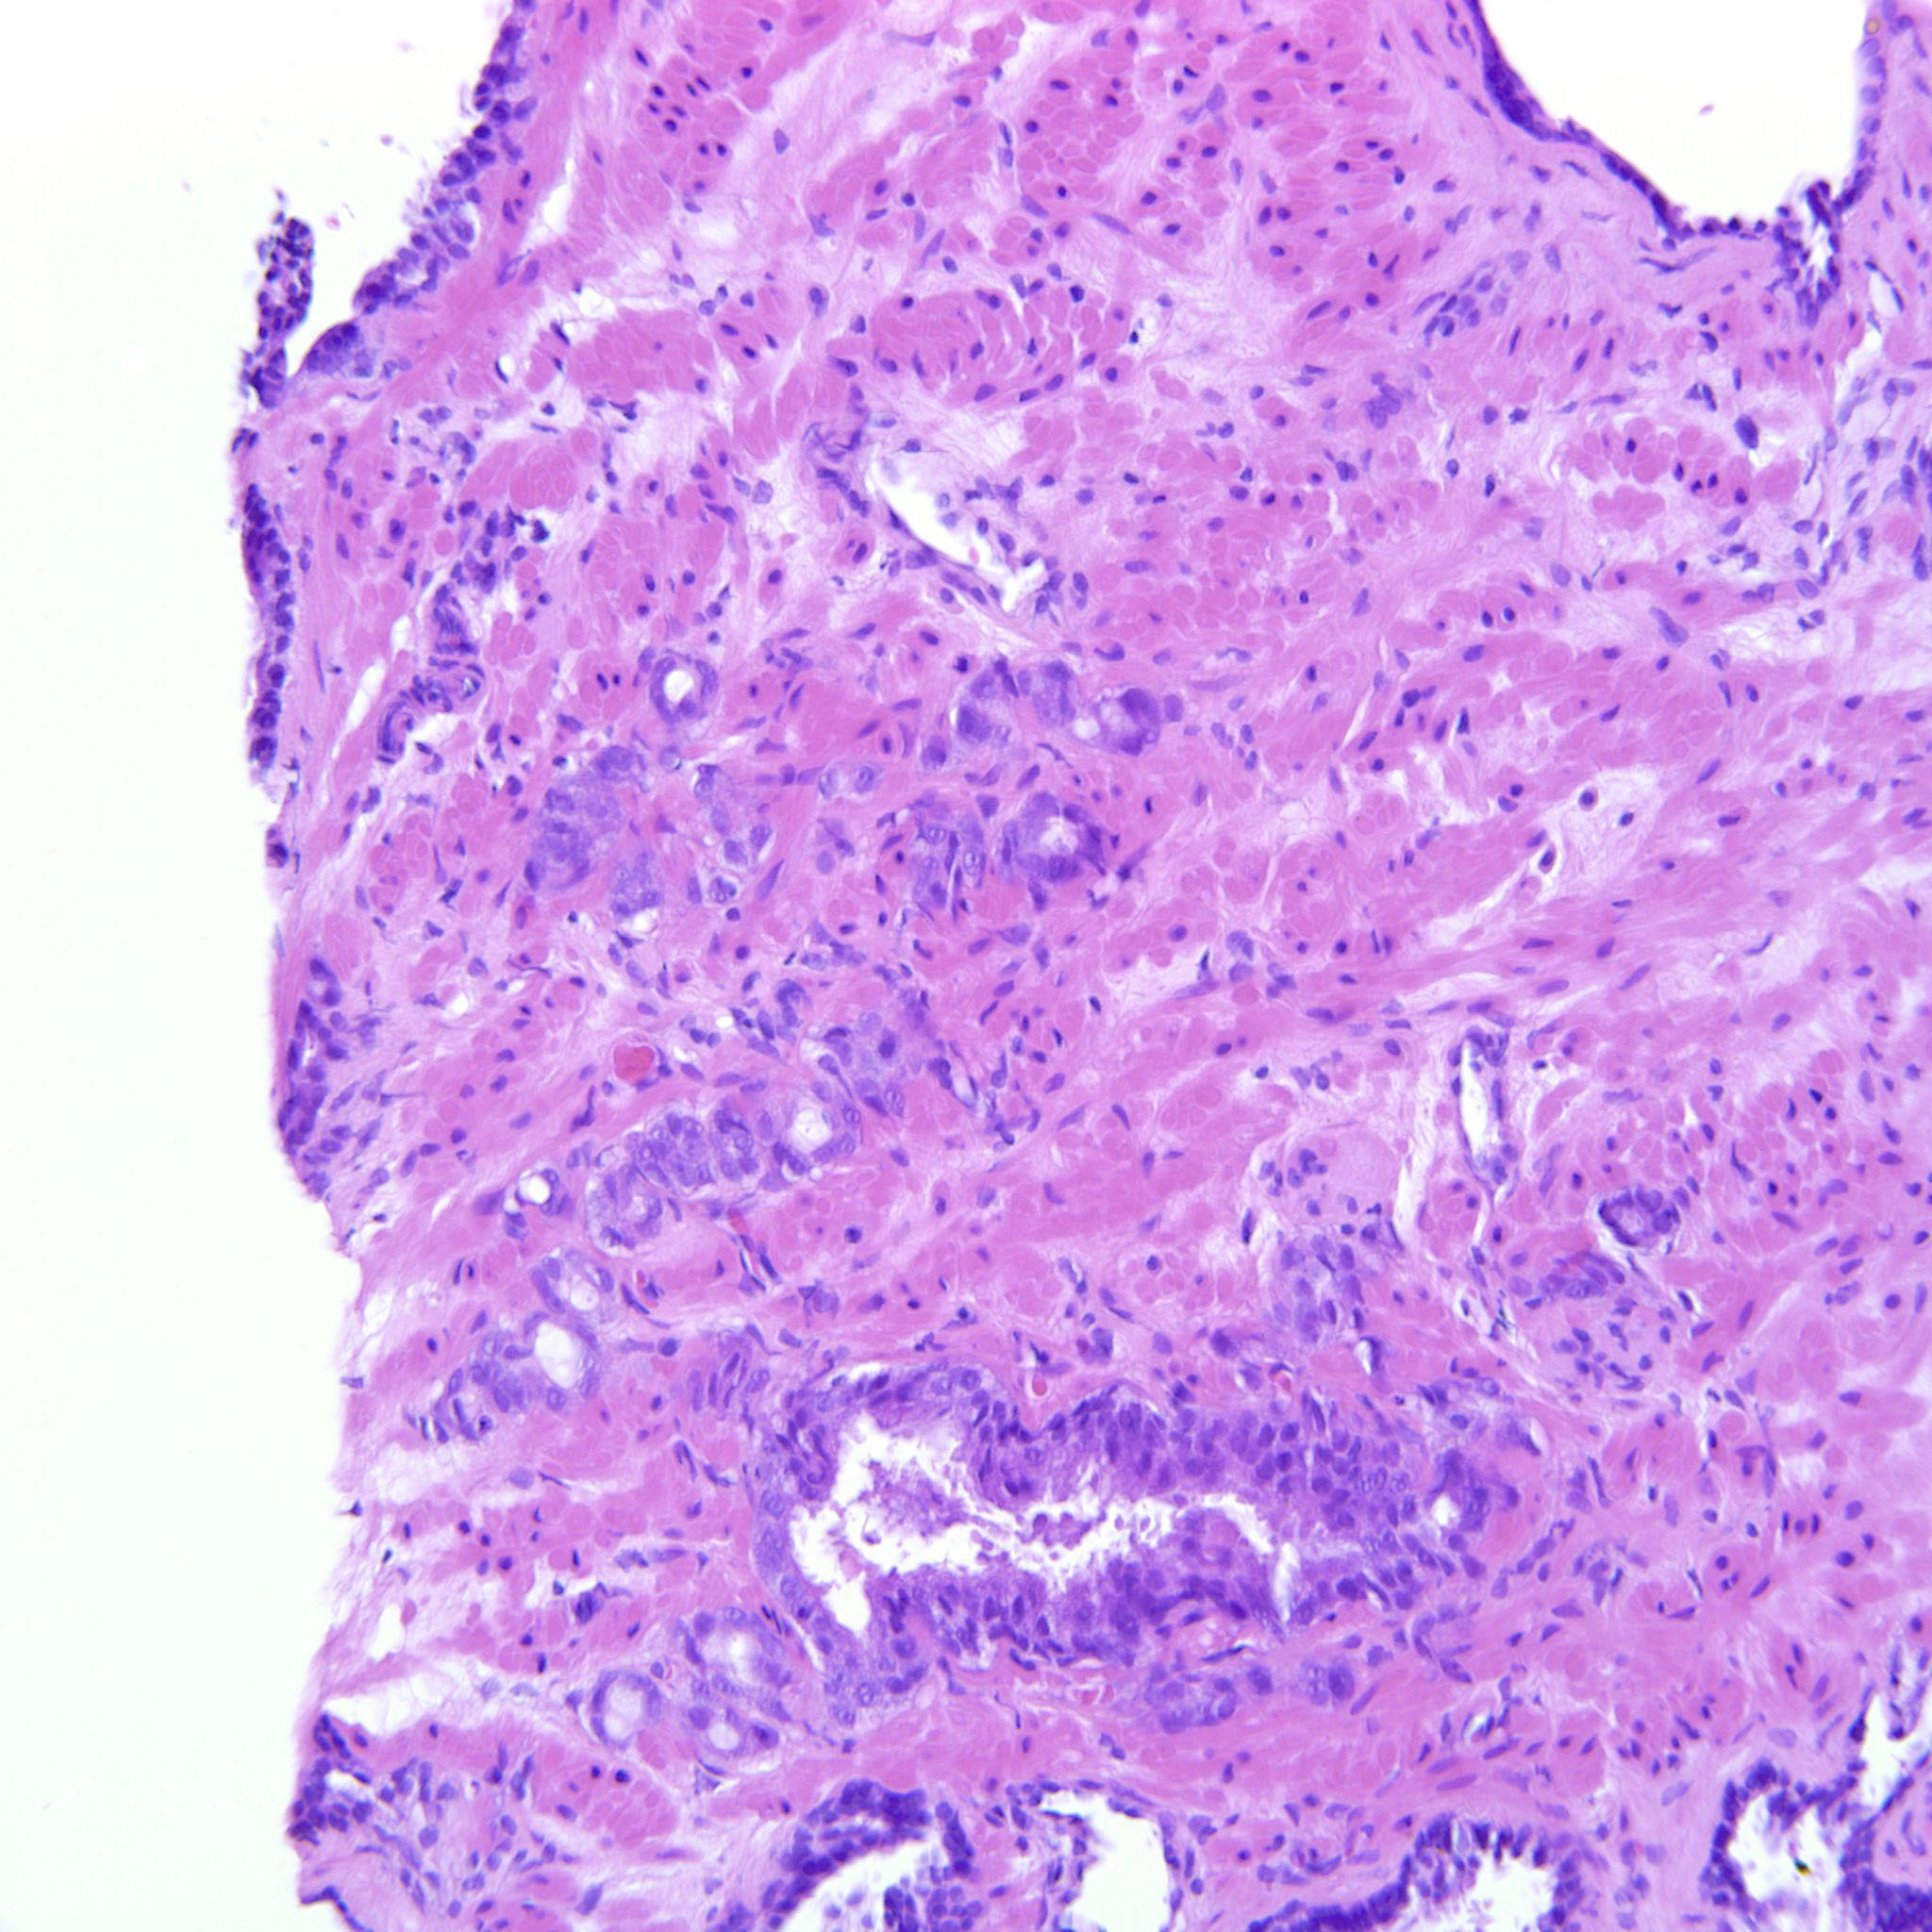

Prostate cancer grading

Case ID: 685